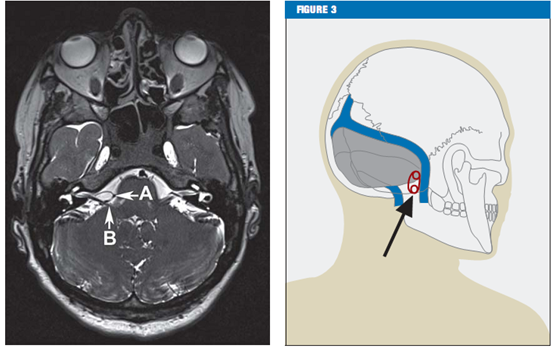

临床特征对于面肌痉挛的诊断至关重要。能帮助诊断的其他方法包括肌电图(EMG)[13]和核磁共振成像(MRI)。核磁共振成像(MRI)还是一个很有用的工具,它可以排除小脑桥脑角中的病理性改变,如肿瘤和脑干损伤。高分辨率T2-序列(注:一种核磁共振技术的术语,是一种成像序列)对显示可能的血管压迫非常有效,如轴面剥离稳态构成干扰(CISS)序列,这样就可以看到脑脊液、神经、和血管的高分辨率的视野(figure 2)。

Figure 2 CISS序列的轴面显示脑干部位后下小脑动脉(箭头A)压迫面部神经(箭头B)

Figure 3图形显示乙状窦后入路开颅位置

在大多数病例中,小脑右下动脉(inferior posterior cerebellar artery,PICA)或小脑前下动脉(inferior anterior cerebellar artery ,AICA)是压迫的主因。很少有椎动脉或这些动脉共同引发的压迫。在很罕见的病例中,也有静脉引发压迫的报道。